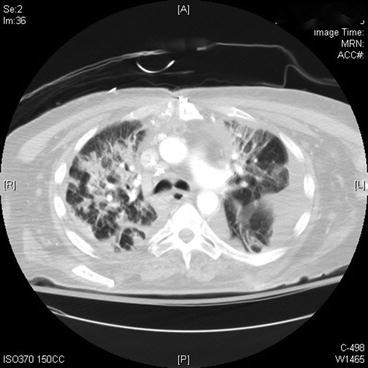

Fig. 47.2 Chest computed tomography

What do the images above show and what is the differential diagnosis based on the appearance seen in the images above?

The chest X-ray (Fig. 47.1) shows diffuse bilateral coalescent opacities, whereas the CT chest (Fig. 47.2) shows ground-glass opacification, reflecting an overall reduction in the air content of the affected lung. It is also possible to visualize bronchial dilatation within areas of ground-glass opacification. Differential diagnosis include (a) ARDS, (b) congestive heart failure, (c) pulmonary hemorrhage, (d) pneumonia, (e) transfusion-related acute lung injury, and (f) non-cardiogenic pulmonary edema.

The Berlin definition, dated 2012, states that acute respiratory distress syndrome is an entity characterized by hypoxemia and stiff lungs that occurs within a week of a known clinical insult or new/worsening respiratory symptoms. It presents with bilateral opacities on the chest X-ray involving at least three quadrants that are not fully explained by effusions, atelectasis, or nodules. Chest computed tomography (CT) findings are opacification that is denser in the most dependent regions as compared to more normal and hyper-expanded lung in the nondependent ones. In addition, CT chest shows widespread ground-glass attenuation, which is a nonspecific sign that reflects an overall reduction in the air content of the affected lung. Respiratory failure in ARDS must not be fully explained by cardiac failure, and an objective assessment for exclusion of such cause may be necessary by echocardiography. Finally, ARDS is classified as mild, moderate, or severe based on PaO2/FiO2 ratio and PEEP. If PaO2/FiO2 ratio is between 200 and 300 mmHg with PEEP ≥5, it is classified as mild. If PaO2/FiO2 ratio between 100 and 200 mmHg with PEEP ≥5, it is moderate. PaO2/FiO2 ratio less than 100 mmHg with PEEP ≥5 is classified as severe. Note that the term acute lung injury has been removed, as well as the requirement of pulmonary capillary wedge pressure ≤18 mmHg [1].